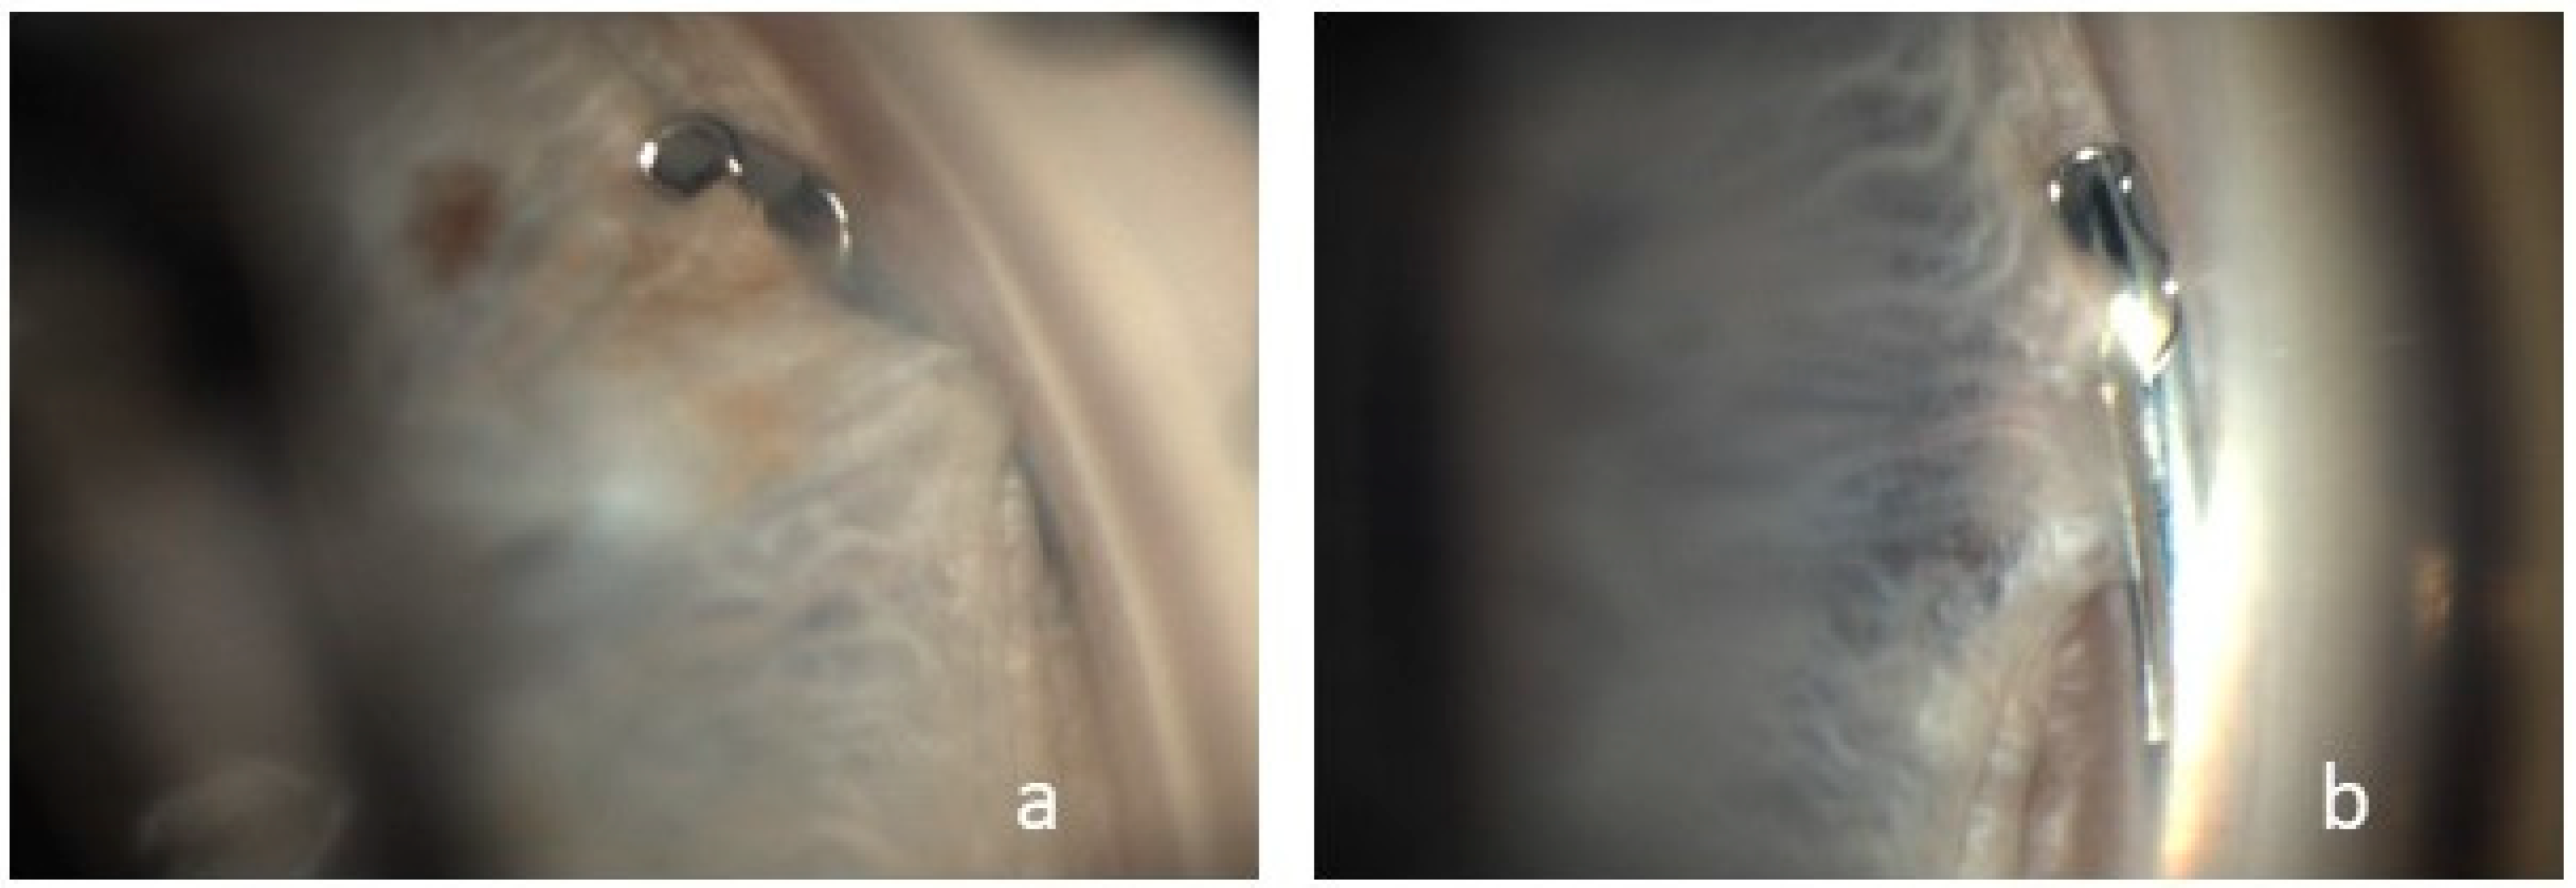

Figure 4.

Visualization of two cases (a,b) of peripheral synechiae between the iris and the proximal tip of the Hydrus® Microstent.

Peripheral synechiae between the iris and the implant without obstruction was observed in four cases (Figure 3).

Peripheral anterior synechiae with device occlusion was reported as a cumulative event in 3.5 cases at two years and 5.4 cases at five years. As in the prospective, randomized study by Pfeiffer et al. and in the COMPARE study by Ahmed et al., we were able to demonstrate the formation of focal peripheral anterior synechiae, which is also listed in the Hydrus® Manual as the most frequent complication of combined MIGS and cataract surgery with a prevalence of 40% [5,22,23]. Pfeiffer et al. followed their patients for 2 years and reported synechiae in 12% of their patients in the first year, increasing to 18.8% in the second year [22]. In our study with a shorter follow-up, there were four cases in which we observed peripheral synechiae in the proximal inlet area. The patients in our study cohort in whom synechiae formation was visualized were examined by 360-degree gonioscopy at a mean interval of 278.25 days, suggesting that synechiae formation may increase in the postoperative course. In addition to synechiae formation, Ahmed et al. described tissue adhesions to the iris as a postoperative side effect, which in one patient had to be removed by yttrium–aluminum–garnet laser treatment. In none of these cases did the IOP evolution indicate implant occlusion [8]. None of the eyes included in our study required secondary surgical intervention.